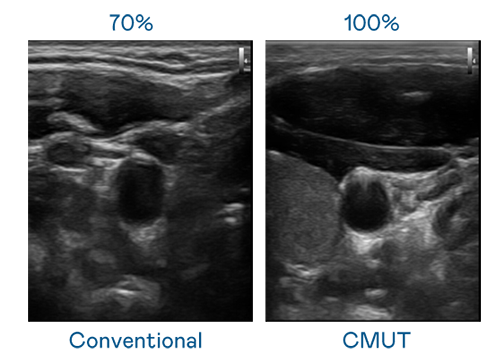

CMUT 技术是一种用电容式微机电元件来产生超音波讯号的技术。与传统 PZT 压电式技术相比,CMUT 频宽增加 30%,更宽频的超音波讯号让影像解析度大幅提升,是实现高影像品质医疗超音波扫描、促进精准医疗发展的关键技术。

大频宽带来超清晰影像

超音波影像的解析度高低,首先取决于探头能发出的讯号频宽。NG28电子 CMUT 可提供高清晰的超音波讯号,提供高频宽、高灵敏度、影像纹理细节更高的超音波影像,协助医护人员缩短影像判读时间及利用精准的医疗影像进行诊断。